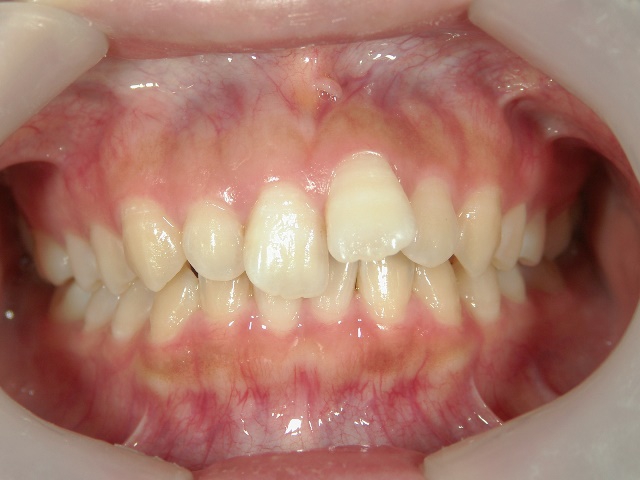

矯正歯科 治療後 正面